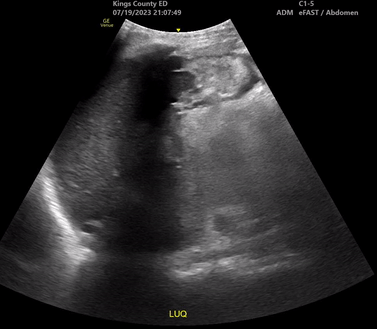

Sono of the Week: 8/3/23

Hemoperitoneum